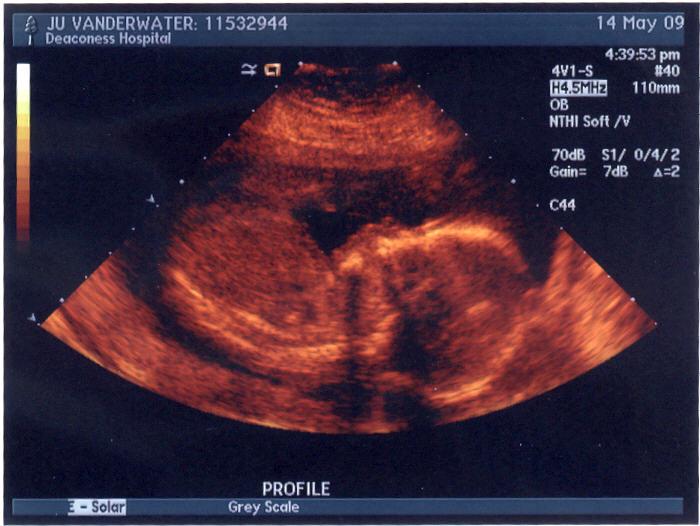

Our baby V's gorgeous profile pics. :D (They're the same, just different color. Check out the nose and the lips!! Hope the baby has Daddy's perfect nose...) Image Image Add new comment Your name Email The content of this field is kept private and will not be shown publicly. Homepage Subject Comment About text formats Leave this field blank